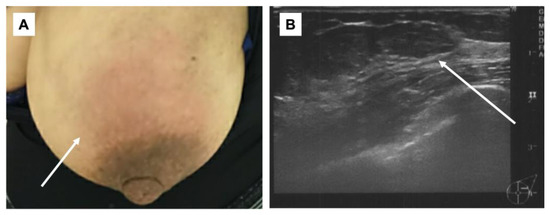

On the second day of the 25th week of pregnancy, the patient developed a tenderness accompanied by erythema on both soles of her feet. Seeking further assistance, she consulted a dermatologist (Figure 1). Initially, the dermatologist diagnosed her with, and treated her for, plantar fasciitis and further prescribed an ointment for treatment. On the same day, the patient was referred to our department for investigation regarding the possible presence of breast cancer owing to a lack of improvement in her symptoms of mastitis. Her height was 155.0 cm and she weighed 59.8 kg. During the physical examination, erythema, pain, and induration were observed in the left breast. Echographic findings suggested pyogenic mastitis (Figure 2A,B). An incision was made to drain the lesion, and a Penrose drain was inserted during the follow-up observation. Cephem antibiotics and anti-inflammatory analgesics were then administered.

Figure 1.

Physical examination. Erythema on bilateral plantar surfaces (arrow).

Figure 2.

Physical examination/mammary echography. (A): Redness was observed in the left breast (arrow); (B): internal hypo-absorption area with some dots of hyper-absorption area was observed. The border was clear, and inflammatory disease including abscess was suspected (arrow).